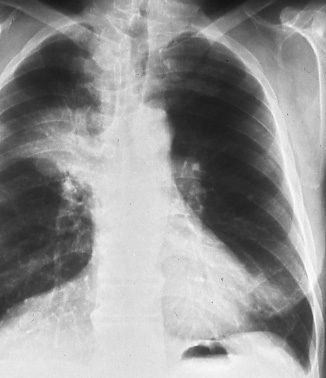

Fig.

40: Posterior-anterior

chest radiograph shows

right upper lobe bronchogenic

carcinoma and enlarged

hilar nodes on the right,

T2 N1 M0, stage IIB. |